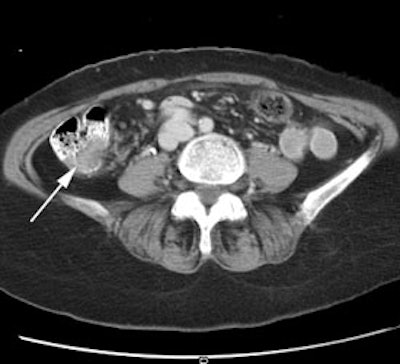

Recurrent colorectal cancer: The patient shown below had a history of colon cancer and a rising CEA level. FDG PET exam revealed a site of tracer uptake in the mesentery (black arrows) which corresponded to an enlarged lymph node seen retrospectively on CT scan (white arrow). |

|